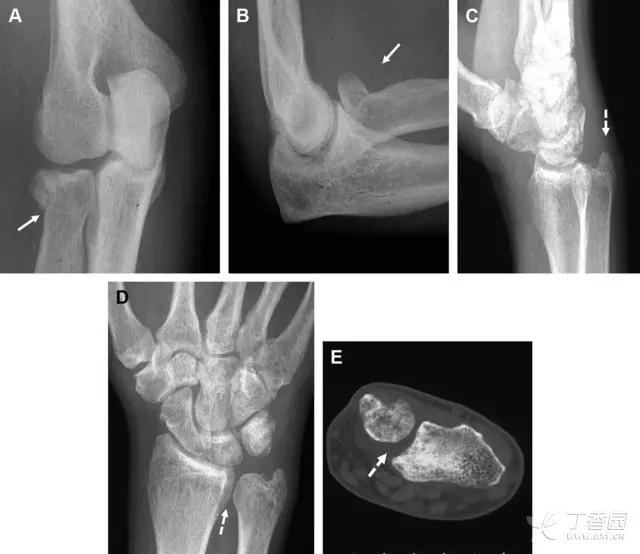

一位足球运动员的 Segond 骨折。A 正位片示关节线下方胫骨外侧皮质撕脱(箭头)。B MRI 冠状位 T1 加权像示附着于髂胫带的骨折碎片(空箭头)(来源:Radiol Clin N Am 53 (2015) 737–755,YU,Ohio)

一位足球运动员的反向 Segond 骨折。A 正位片示关节线处的胫骨内侧见一细小骨折片(箭头)。B MRI 冠状位 T1 加权像示骨折片出现在内侧副韧带关节囊附着处(方框)(来源:Radiol Clin N Am 53 (2015) 737–755,YU,Ohio)